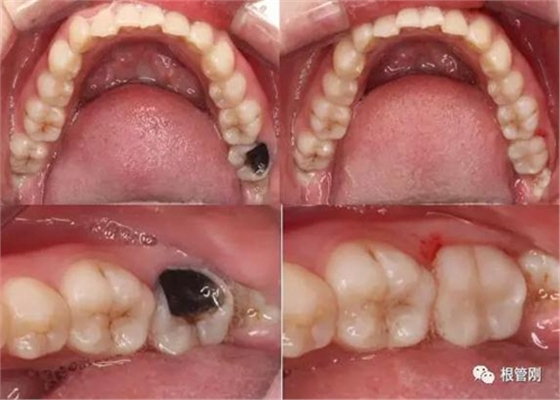

這是一顆嚴(yán)重的蛀牙,顏色發(fā)黑,牙齒的一半已經(jīng)崩解,看到此情此景,也許很多人會想它的神經(jīng)肯定死掉了吧?它還有救嗎?應(yīng)該會做根管治療+牙冠修復(fù)吧?

經(jīng)細(xì)致的詢問病史(有沒有自發(fā)痛,冷熱刺激敏感等)、仔細(xì)的檢查(包括探診,冷診,熱診,叩診以及牙片的檢查不可缺少),綜合各種信息判斷,得出準(zhǔn)確的診斷為深齲,在與患者溝通,患者同意直接樹脂修復(fù)!

深齲離牙髓炎僅一步之遙,也就意味著離根管治療僅一步之遙。于細(xì)微處見知著,于細(xì)小之處見技術(shù)!不管怎樣,除疾病,還健康,是我們的共同初心,盡醫(yī)生所能,也盡患者所能,方能得始終!

早發(fā)現(xiàn),早治療,永遠(yuǎn)是對的!